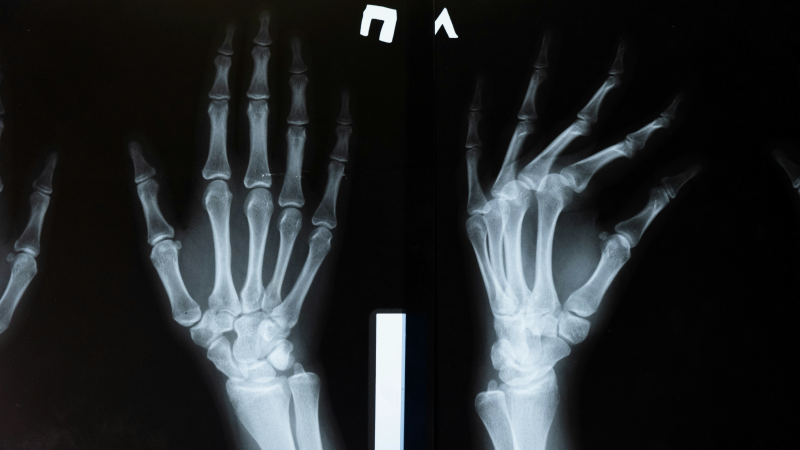

Rx torace, mano e dita, polso, avambraccio, gomito, piede e dita, caviglia, gamba (tibia e perone), ginocchio, scheletro costale.

Da mercoledì 23 ottobre 2024, in 21 strutture sanitarie del territorio dell’Azienda USL di Bologna, sarà possibile accedere direttamente, senza prenotazione, per eseguire radiografie al torace per sospetto di polmonite e radiografie a dita della mano, polso, avambraccio, gomito, piede, dita del piede, caviglia, tibia perone, ginocchio ed emicostato per sospetto di fratture.